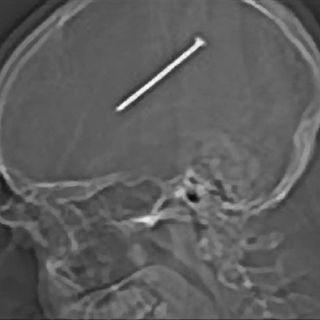

OAK LAWN, ESTADOS UNIDOS (21/ENE/2012).- Gail Glaenzer aún no puede creer que su prometido se haya disparado un clavo en el cráneo sin percatarse de ello, y mucho menos que haya publicado una imagen de rayos X en Facebook mientras iba en la ambulancia que lo trasladó de un hospital a otro para someterlo a una cirugía.

Un par de horas después se le tomó una radiografía, la cual reveló la presencia del clavo, a la mitad del cerebro. Los médicos le dijeron a la pareja que el clavo quedó a milímetros de la zona del cerebro que controla las funciones motoras.